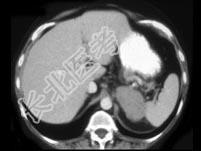

- 单项选择题女,47岁, 满月脸、向心性肥胖伴高血压1月,结合图像, 最可能的诊断是 ( )

A、左肾上腺腺瘤

B、左肾上腺腺癌

C、左肾上腺转移癌

D、左肾上腺嗜铬细胞瘤

E、左肾上腺增生